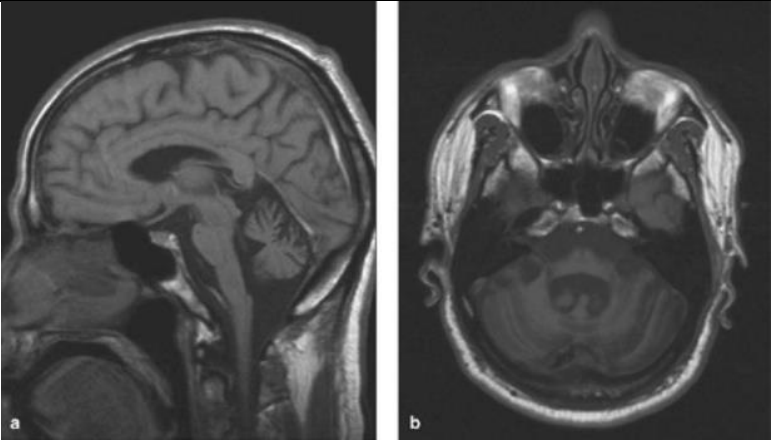

Accurate diagnosis of  SCA type is crucial for determining disease prognosis, genetic counseling, and selecting appropriate treatment MRI scan (sagittal and transverse T 1 -weighted image) of a 72-year-old woman with idiopathic late-onset cerebellar ataxia (ILOCA gradually progressive isolated cerebellar syndrome). Obvious atrophy of the cerebellar vermis, also of the brainstem (5)

Fig 3